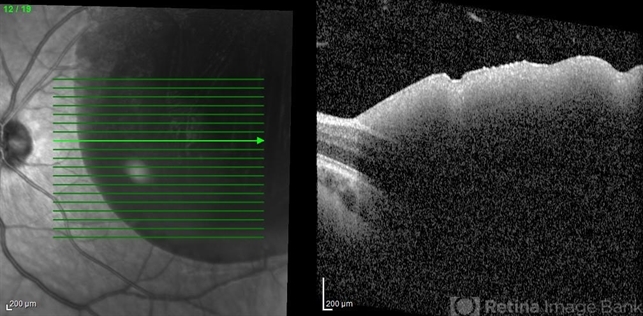

- valsalva retinopathy, OCT

- OCT of a 30 year old man who presented with valsalva retinopathy